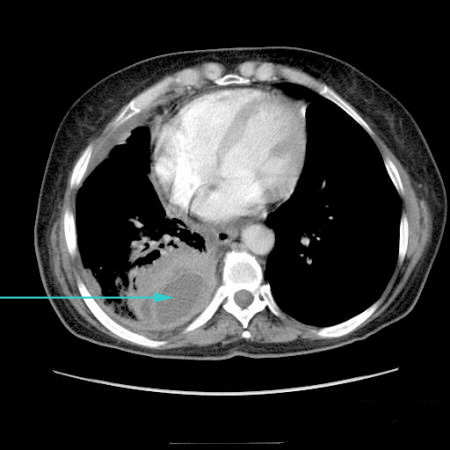

CT scan showing loculated pleural effusion

From the collection of Dr Ami Rubinowitz; used with permission